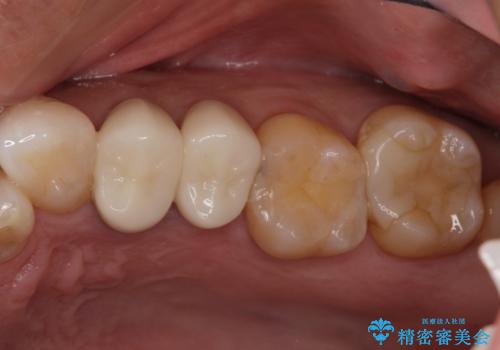

腫れもなくなり、見た目もきれいになったため、右上もご希望されて計3本の歯を治療しました。患者様には大変満足して頂きました。

左上で効果を実感して頂き、その後右上もご希望されました。合計3本の歯を治療しました。

当院では、清潔な治療を徹底し、顕微鏡を使用した精密な治療を行っています。